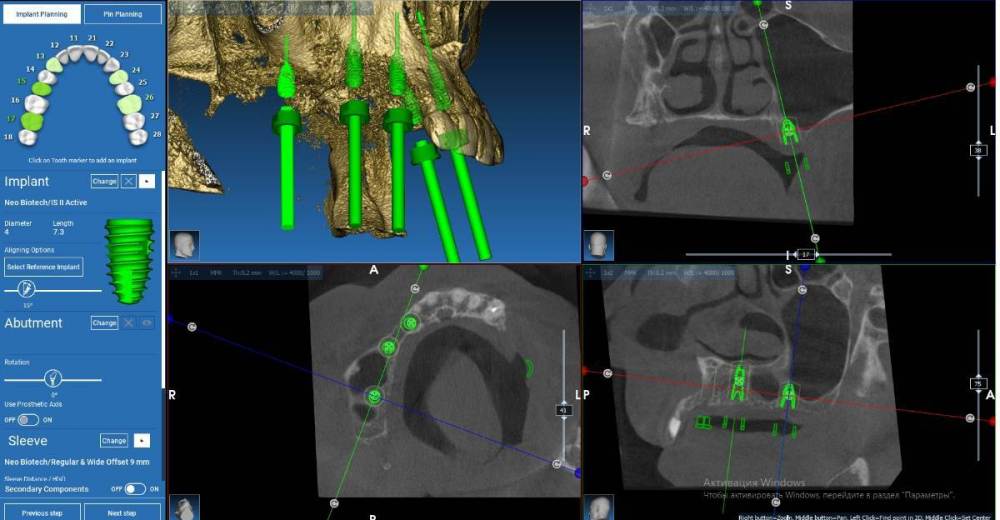

Fin Опубликовано 2 августа, 2022 Поделиться Опубликовано 2 августа, 2022 (изменено) Здравствуйте коллеги. Очень нужен ваш совет с планом лечения. Планирую установить 4 импланта на В.Ч.. В области зубов 2.4 и 2.6 все более менее понятно( 2.4 просто ставить а 2.6 ОСЛ и ставить), а вот в 1 сегменте все значительно сложнее. На данный момент имею три варианта конечно все варианты с навигационным шаблоном: 1.) 1.3 +НКР титановой сеткой (смущает что восстанавливать надо небно) 1.5 под углом и протезом на МЮ с небольшой консолью 1.6 (в виде премоляра) 2. 1.3 все так же либо рискнуть и оставить пару витков открытыми 1.5 имплант 4х10(11,5) и 1.7- 4х 7,3 с ЗСЛ 3 . Может Все таки пора начинать ставить анкилоз и поставить в обл 1.3 3,5х8 с небольшим оголением небной стенки.В остальный местах на этой стороне так же ануилоз. Протезрование делать с уровня МЮ. Благодарю Вас за советы. Скрины 2 сегмента Изменено 2 августа, 2022 пользователем Fin Ссылка на комментарий

Irouil Опубликовано 2 августа, 2022 Поделиться Опубликовано 2 августа, 2022 В первом варианте у вас 1.3 выходит куда-то практически в 1.4, имхо надо чуть медиальнее Я бы не стал там титановую сетку городить, небо - это фактически трехстеночный дефект, сделал бы сосидж вокруг тонкого ФДМ или временной коронки А с остальными винтами почему не открытый синус+импланты? Ну или если заходит закрытый под углом (не очень понятно по скринам), то его + МЮ (и тогда у 1.3 сосидж вокруг мульта) Ссылка на комментарий

Fin Опубликовано 2 августа, 2022 Автор Поделиться Опубликовано 2 августа, 2022 (изменено) 15 минут назад, Irouil сказал: В первом варианте у вас 1.3 выходит куда-то практически в 1.4, имхо надо чуть медиальнее Я бы не стал там титановую сетку городить, небо - это фактически трехстеночный дефект, сделал бы сосидж вокруг тонкого ФДМ или временной коронки А с остальными винтами почему не открытый синус+импланты? Ну или если заходит закрытый под углом (не очень понятно по скринам), то его + МЮ (и тогда у 1.3 сосидж вокруг мульта) Спасибо за ответ. На счет 1.3 вы правы, надо медиальнее, нечаянно выровнял оси имплантов. Вы немного не поняли. Думал поставить 1.5 под углом и на него кослольку небольшую до 6 ки. Да, возможно ОСЛ в области 1,6 будет правильнее и в последующем имплант будут правильнее. Изменено 2 августа, 2022 пользователем Fin Ссылка на комментарий